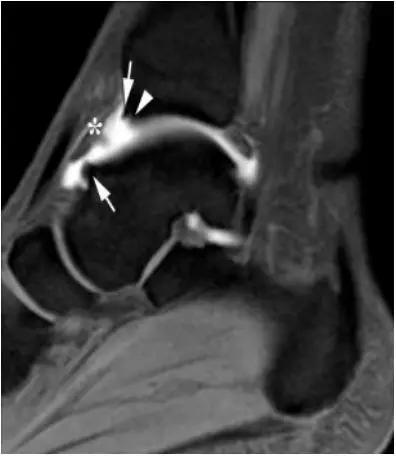

6.后踝撞击综合症:

- 骨性撞击多见,例如距骨后三角骨损伤,距骨或跟骨后突过度增生。软组织撞击表现为后胫腓韧带下部分、横韧带、后踝间韧带的撕裂或肥厚增生。

- 影像学表现为距骨后三角骨的存在或损伤以及距骨后突骨赘形成,导致踝关节跖屈受限,可伴随拇长屈肌肌腱鞘炎症及邻近滑膜不同程度的炎性增生 。

正常后踝韧带;MRI 冠状位T2-FLAIR示踝间后韧带(长箭)

男,11岁,自述后踝下方疼痛,活动时为甚,并有一突起。

- MRI 检查示距后三角骨及周围软组织有水肿信号,距后三角骨和距骨之间正常的低信号纤维连接中断,出现液性信号。

3、MR表现:

- 三角籽骨或距骨后三角结构模糊和变形,T1WI信号降低, T2WI信号升高,

- 周围脂肪水肿,

- 踇趾长屈肌腱信号升高,见鞘膜积液,

- 胫骨后下跟骨上缘骨结构形态变化和信号异常,

- 三角籽骨和距骨退行性囊变。